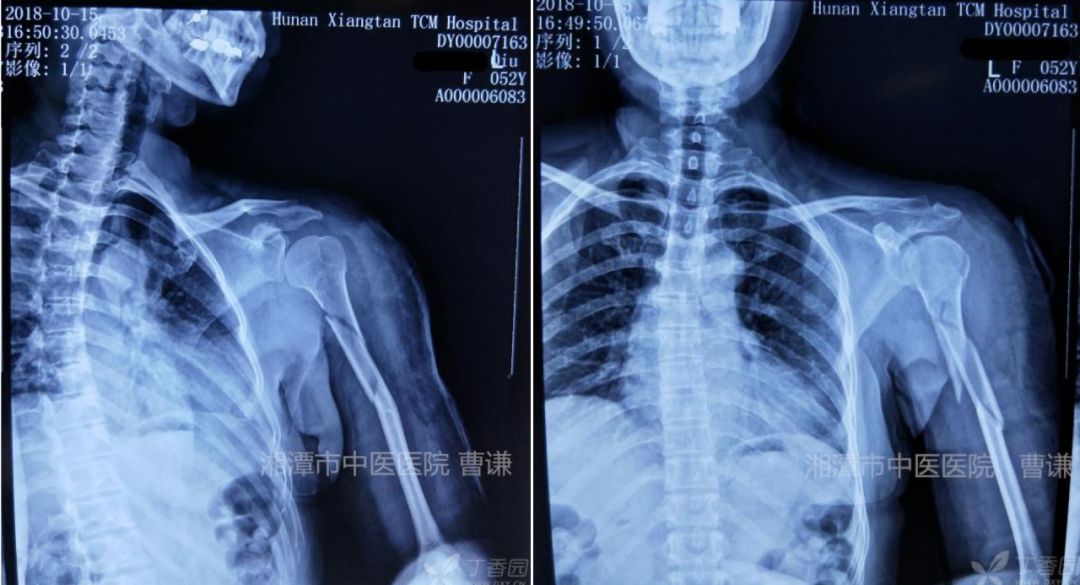

外院 X 线片示肱骨中上段骨折,骨折端粉碎(点击可查看大图)